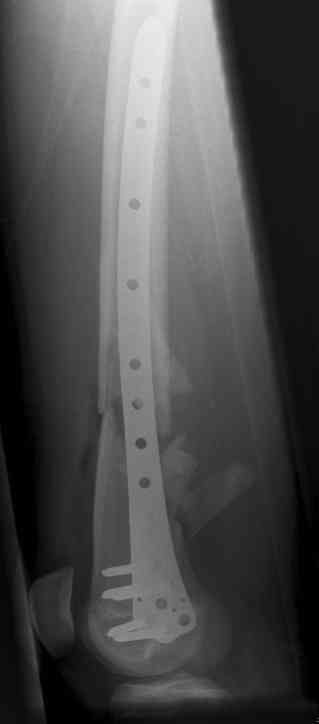

16 yr old boy, high energy motorcycle trauma trauma in July 2005 with:

- hip dislocation + acetabular fracture L

- distal femoral fracture L

- tibial shaft fracture L

- metatarsal fractures L

july 05: LISS femur, LCP plate tibia, double recon. plate post. acetabulum

oct 05: cancellous bone graft femur

aug 06: blade plate + bone graft

nov 06: revision blade plate

feb 07: retrograde nail + bone graft + BMP

may 07: dynamisation nail

sept 07: locking screw removal (max. dynamisation reached)

nov 07: persistant non-union distal femur; other fractures healed uneventfully.